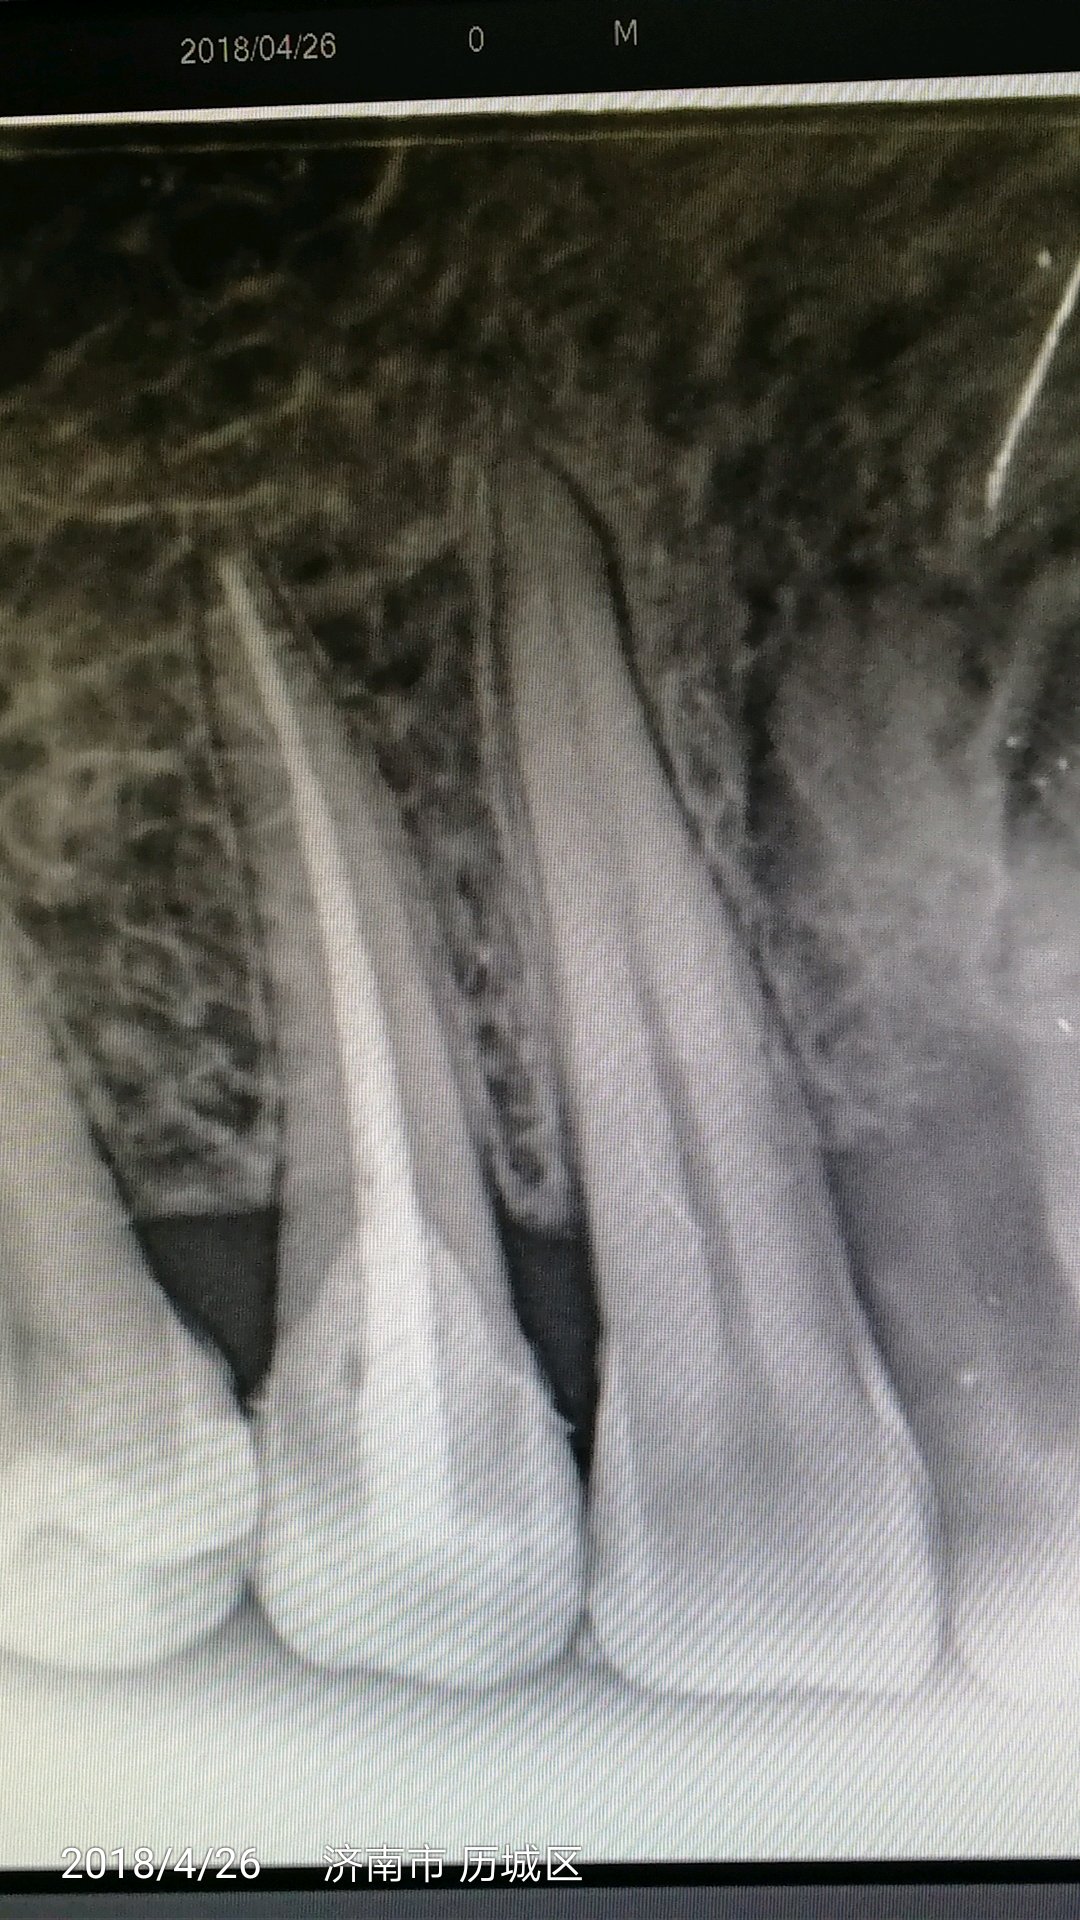

老学长的作品🌝

老弟,有证没?一个单根很冲这么嚣张?!哥这种都是一次性根冲的。有能耐那上67的片子。